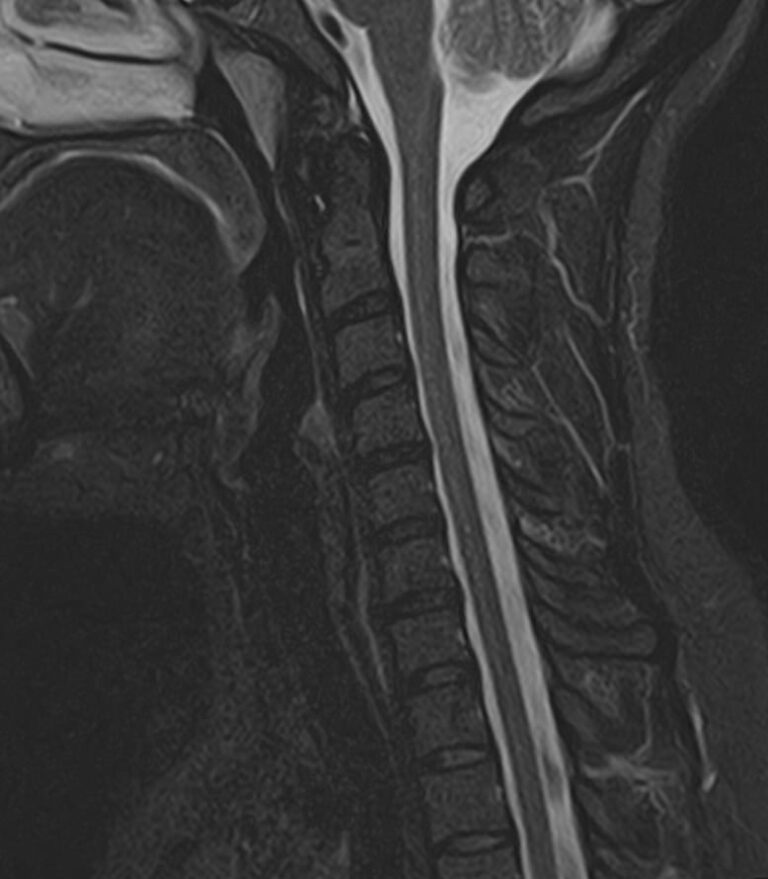

В клинике «Доступная медицина» можно пройти комплексное обследование, включающее в себя два протокола сканирования близко расположенных друг от друга анатомических областей – шейного отдела позвоночника и головного мозга. Метод комплексного обследования оценивает состояние всех структур головного мозга и самого верхнего сегмента позвоночного столба, который включает в себя 7 шейных позвонков, спинной мозг с отходящими от него нервными корешками и окружающими мягкими тканями.

Сканирование проводится на современном высокопольном магнитно-резонансном томографе закрытого типа TOSHIBA VANTAGE TITAN 1,5 Тесла. Магнитно-резонансный томограф производит послойное сканирование исследуемой зоны в разных плоскостях, затем при помощи компьютерных программ преобразует полученные данные в трехмерные изображения с высокой степенью детализации.

Что показывает МРТ головного мозга + шейного отдела позвоночника

В рамках проведения данного комплексного исследования можно выявить:

• остеохондроз, спондилоартроз, спондилез, межпозвонковые грыжи, унковертебральный артроз, сколиоз, усиленный или выпрямленный лордоз как нарушение статической функции позвоночника, травмы, аномалии позвоночника.